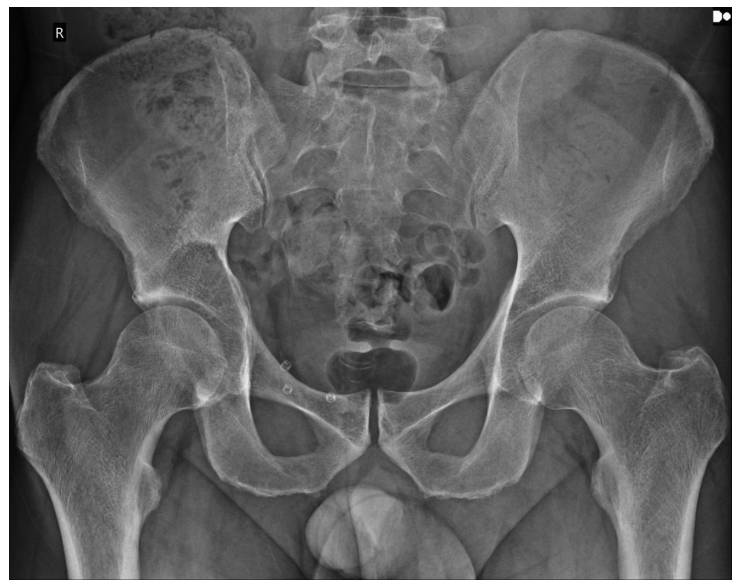

Ameliyat Öncesi: Röntgende sağ asetabulumda sınırları nispeten belirli litik lezyon görülmekte